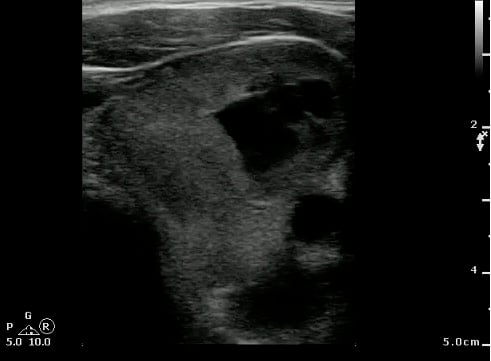

- Scanning technique20

- Probe selection:

- A 5.0 to 10.0 MHz curved array intracavitary probe is used to evaluate a suspected PTA for intraoral ultrasound. Alternatively, a high frequency linear array transducer can be used for transcervical approach, especially in children or patients with severe trismus.

- Scanning approach:

- Cover intracavitary probe with either a proprietary cover, glove or condom.

- Place probe into the oral cavity over the area in question.

- The peritonsillar area should be systematically scanned in both long and short axes.

- Color Doppler should be used to identify the depth of the carotid artery and surrounding vessels.

- Alternatively, place the linear array transducer inferior and adjacent to the angle of the mandible with rotation of the head to the contralateral side. The tonsil is deep to the submandibular gland, medial to the facial vessels, and lateral to the tongue.

Video 24. Scanning tonsils

- Normal findings

- Normal Tonsil

- The ovoid tonsils appear striated with hyperechoic bands and hypoechoic parenchyma, as well as lobulated margins.

- Figure 42 and 43. Normal Tonsil